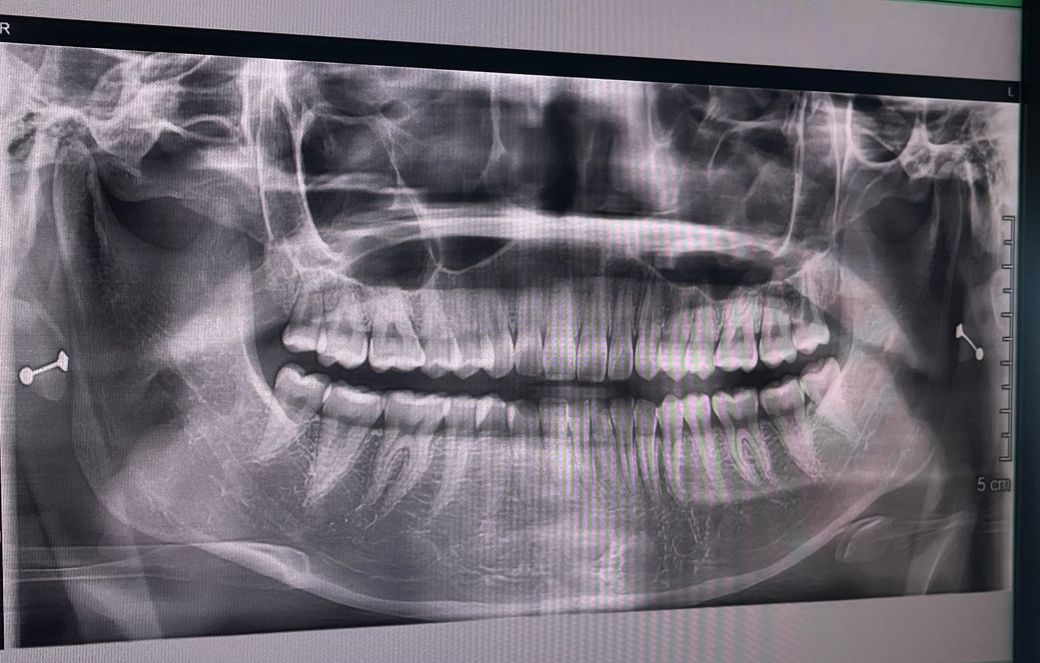

턱관절 엑스레이 제발 한번만 봐주세요...ㅠㅠ

2달 전에 이빨에 충치가 생긴 것 같아서

하루동안 입을 크게 벌리고 이빨을 계속 확인했더니

그 날 이후로 1주 좀 넘게 턱이 뻐근하고

약간의 딱소리가 나는 정도였고 그 후에는 소리도 안나고 괜찮아서 병원을 안갔습니다

근데 이번 추석연휴에

한쪽 팔을 들고 하품하다가 살면서 처음으로

오른쪽 턱에서 우드득 소리가 나면서

턱이 벌어지는 느낌이 났습니다

그러고 놀라서 몇번 입을 열었다 닫았더니

소리 자체는 또 많이 나진 않았습니다

그래도 불안해서 구강악을 봐주시는 치과로 갔는데

엑스레이 촬영을 하고

턱쪽을 여러번 눌러보시고

어디가 아픈지 확인해주셨습니다

통증은 심하진 않았지만 오른쪽 귀앞쪽을 눌렀을 때

통증이 좀 있었습니다 (현재는 통증 없음)

별 문제가 없다는 느낌으로 말씀해주시고

그냥 살짝 삔 거라는 그런 말을 해주셨습니다

병원에서는 물리치료 + 소염제, 근육이완제 같은 약을 5일치 처방해주셔서 먹었고

약을 오늘 마지막으로 먹었는데

지금은 가만히 있을 때는 괜찮고

음식을 먹고나 양치를 하고는 약간 뻐근한정도 입니다

1. 양쪽 턱관절 마모되었나요? (양쪽 상태가 궁금해요)

2. 아래턱을 윗니보다 앞으로 내밀면 약

간의 딱소리가 납니다 (이것도 문제가 있는걸까요? 심하진 않습니다 이런 행동을 자제하려 하고있습니다 ㅠㅠ)

3. 디스크가 빠졌는지 턱관절은 어때보이나요?

4. 엑스레이상 충치는 있어보이나요?

5. 사랑니 4개가 모두 났는데 엑스레이상 발치를 해야할것같나요?

• 1번 째 사진

1. 양쪽 턱관절 다 마모는 눈에 띄지 않습니다

2. 과두가 올바르지 않은 위치에서 개폐구가 이뤄지면 누구나 소리가 나고 뻐근합니다

애초에 아래 턱을 내밀고 그러지 마세요

3. 정상입니다

4. 파노라마 사진에서는 충치 정밀하게 판독 안합니다 눈에띄게 큰 충치는 없습니다

5. 사랑니 4개 모두 발치 불필요합니다 아주 바르게 잘 났습니다 관리만 잘해주세요